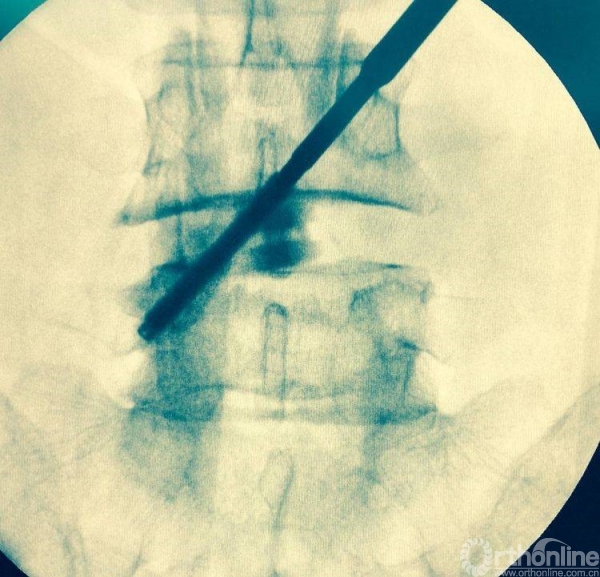

植入椎板钉、开路椎、扩展管、克氏针以及动力钻等应用

植入经皮椎弓根钉并加压